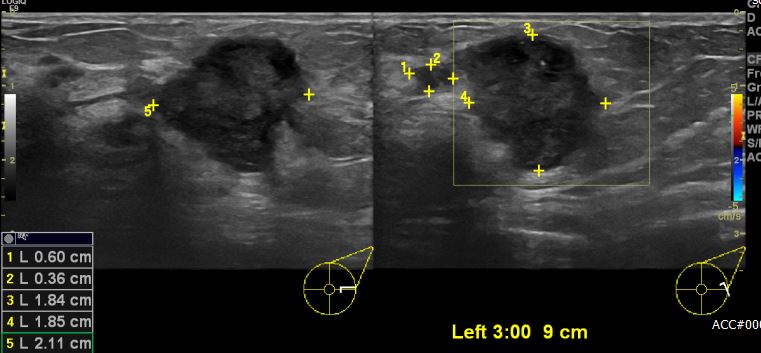

건강검진상 이상 소견으로 내원하신 50대 여성분으로 좌측 3시 방향에서 9cm 떨어진

거리에 의심스러운 멍울 조직검사 시행하여 좌측 침윤성 유관암 진단 되었습니다.